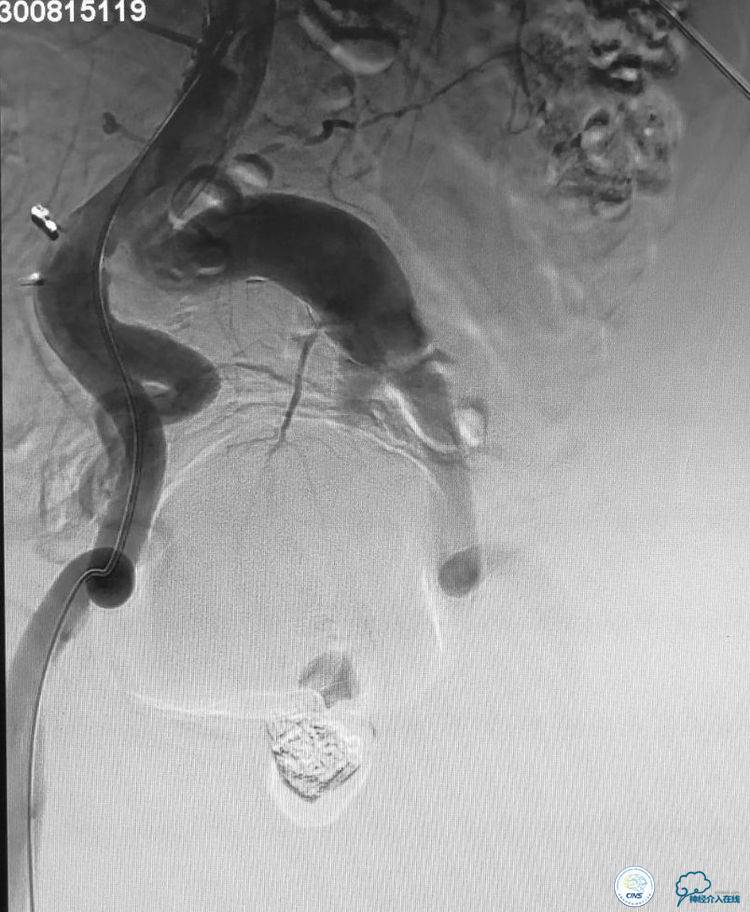

▼扩张后狭窄明显改善。

▼释放4.5x20 Neuroform支架。

▼将微导管超选择到动脉瘤腔内。

▼2个微导管到位。

▼分别进行栓塞。